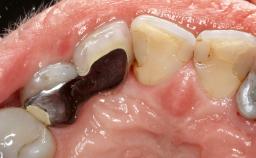

Open-Flap Debridement for the Management of Peri-Implant Mucositis Associated with Excess Cement

A 79-year-old female patient was referred to the Department of Periodontology of the University of Bern, Switzerland by her private dentist in May 2019. She had been rehabilitated in May 2005 with two tissue-level implants (Institut Straumann AG, Basel Switzerland) at sites 13 and 15, supporting a three-unit cemented fixed dental prosthesis (FDP). The metal-ceramic FDP had been cemented permanently with a glass-ionomer cement (Ketac Cem; 3M ESPE, Seefeld, Germany). Implant 13 had been diagnosed with peri-implant mucositis by the referring dentist in the course of regular supportive therapy. The patient was in good general health, did not smoke, and exhibited good self-performed plaque control.